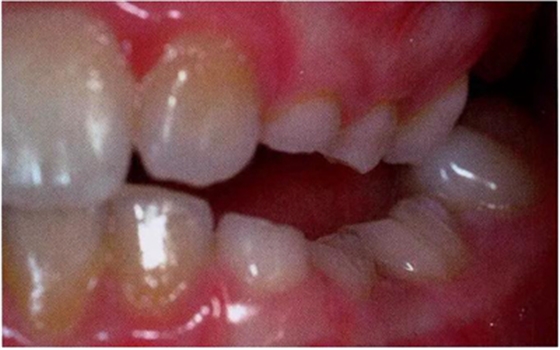

圖3:重度下沉的臨床像